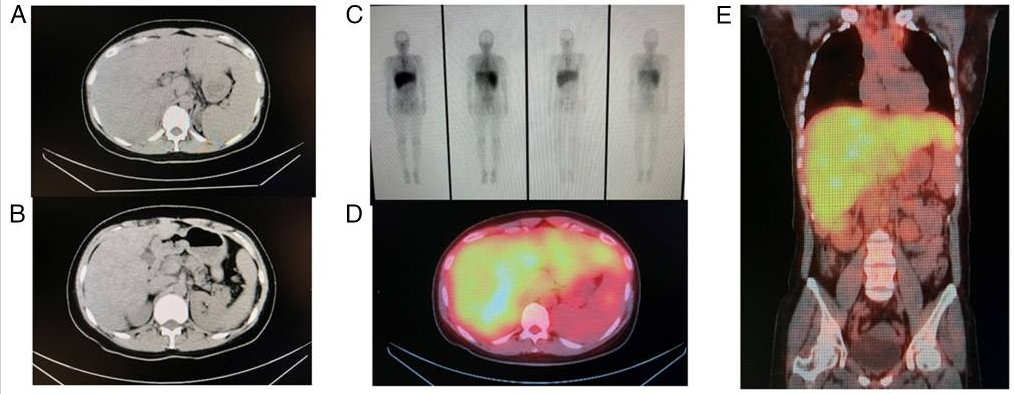

发现才5天的肺结节为何就考虑必为肺癌?怎样的腺癌不必基因检测?

病史摘要:患者主因“发现肺部占位 5 天”入院。5 天前体检肺部 CT 发现肺结节,至我院复查胸部 CT 提示右肺中叶部分实性结节,待排肿瘤性病变。有咳嗽咳痰、乏力纳差症状,无痰中带血等不适。既往有 3 年余高血压病史,最高血压 140/80mmHg。 诊疗过程:体格检查未提及。PET-CT 检查考虑右中叶结节恶性可能性大,纵隔与肺门淋巴结炎性可能性大。气管镜病理确诊

浸润性腺癌

典型

浏览 1231 | 讨论 0